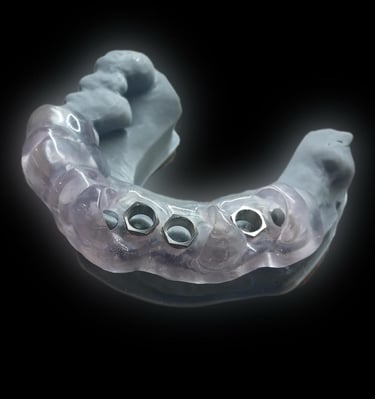

3.A partir del diseño digital, se obtiene una guía quirúrgica para las colocación precisa del implante.